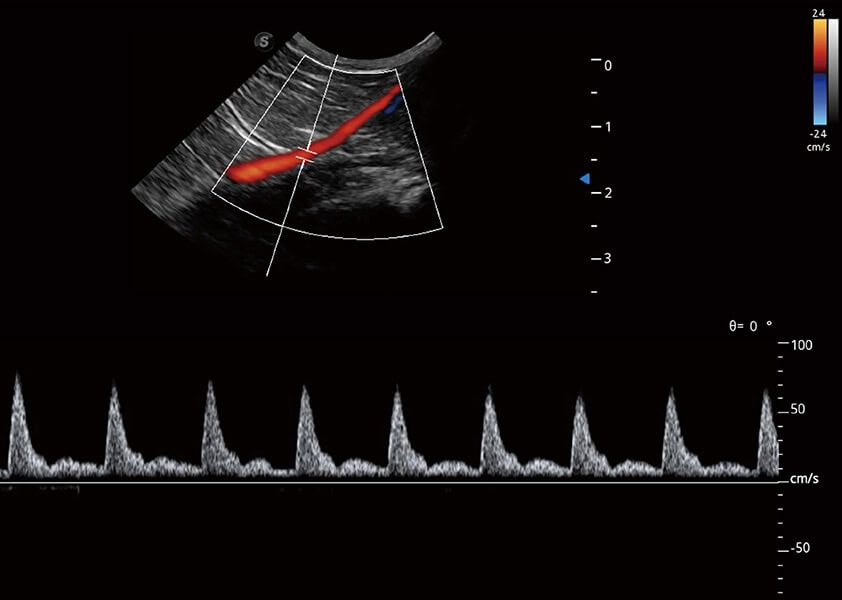

ProPet 60 作為一款高端臺式動物超聲設(shè)備,為動物醫(yī)生的日常診斷提供了一系列貼合動物臨床需求、解決臨床實際問題的高級成像功能。憑借全系列高清探頭,滿足醫(yī)生對腹部、心臟、生殖、淺表、肌骨等成像的所有需求,切實幫助您提升檢查效率,提高診斷信心。